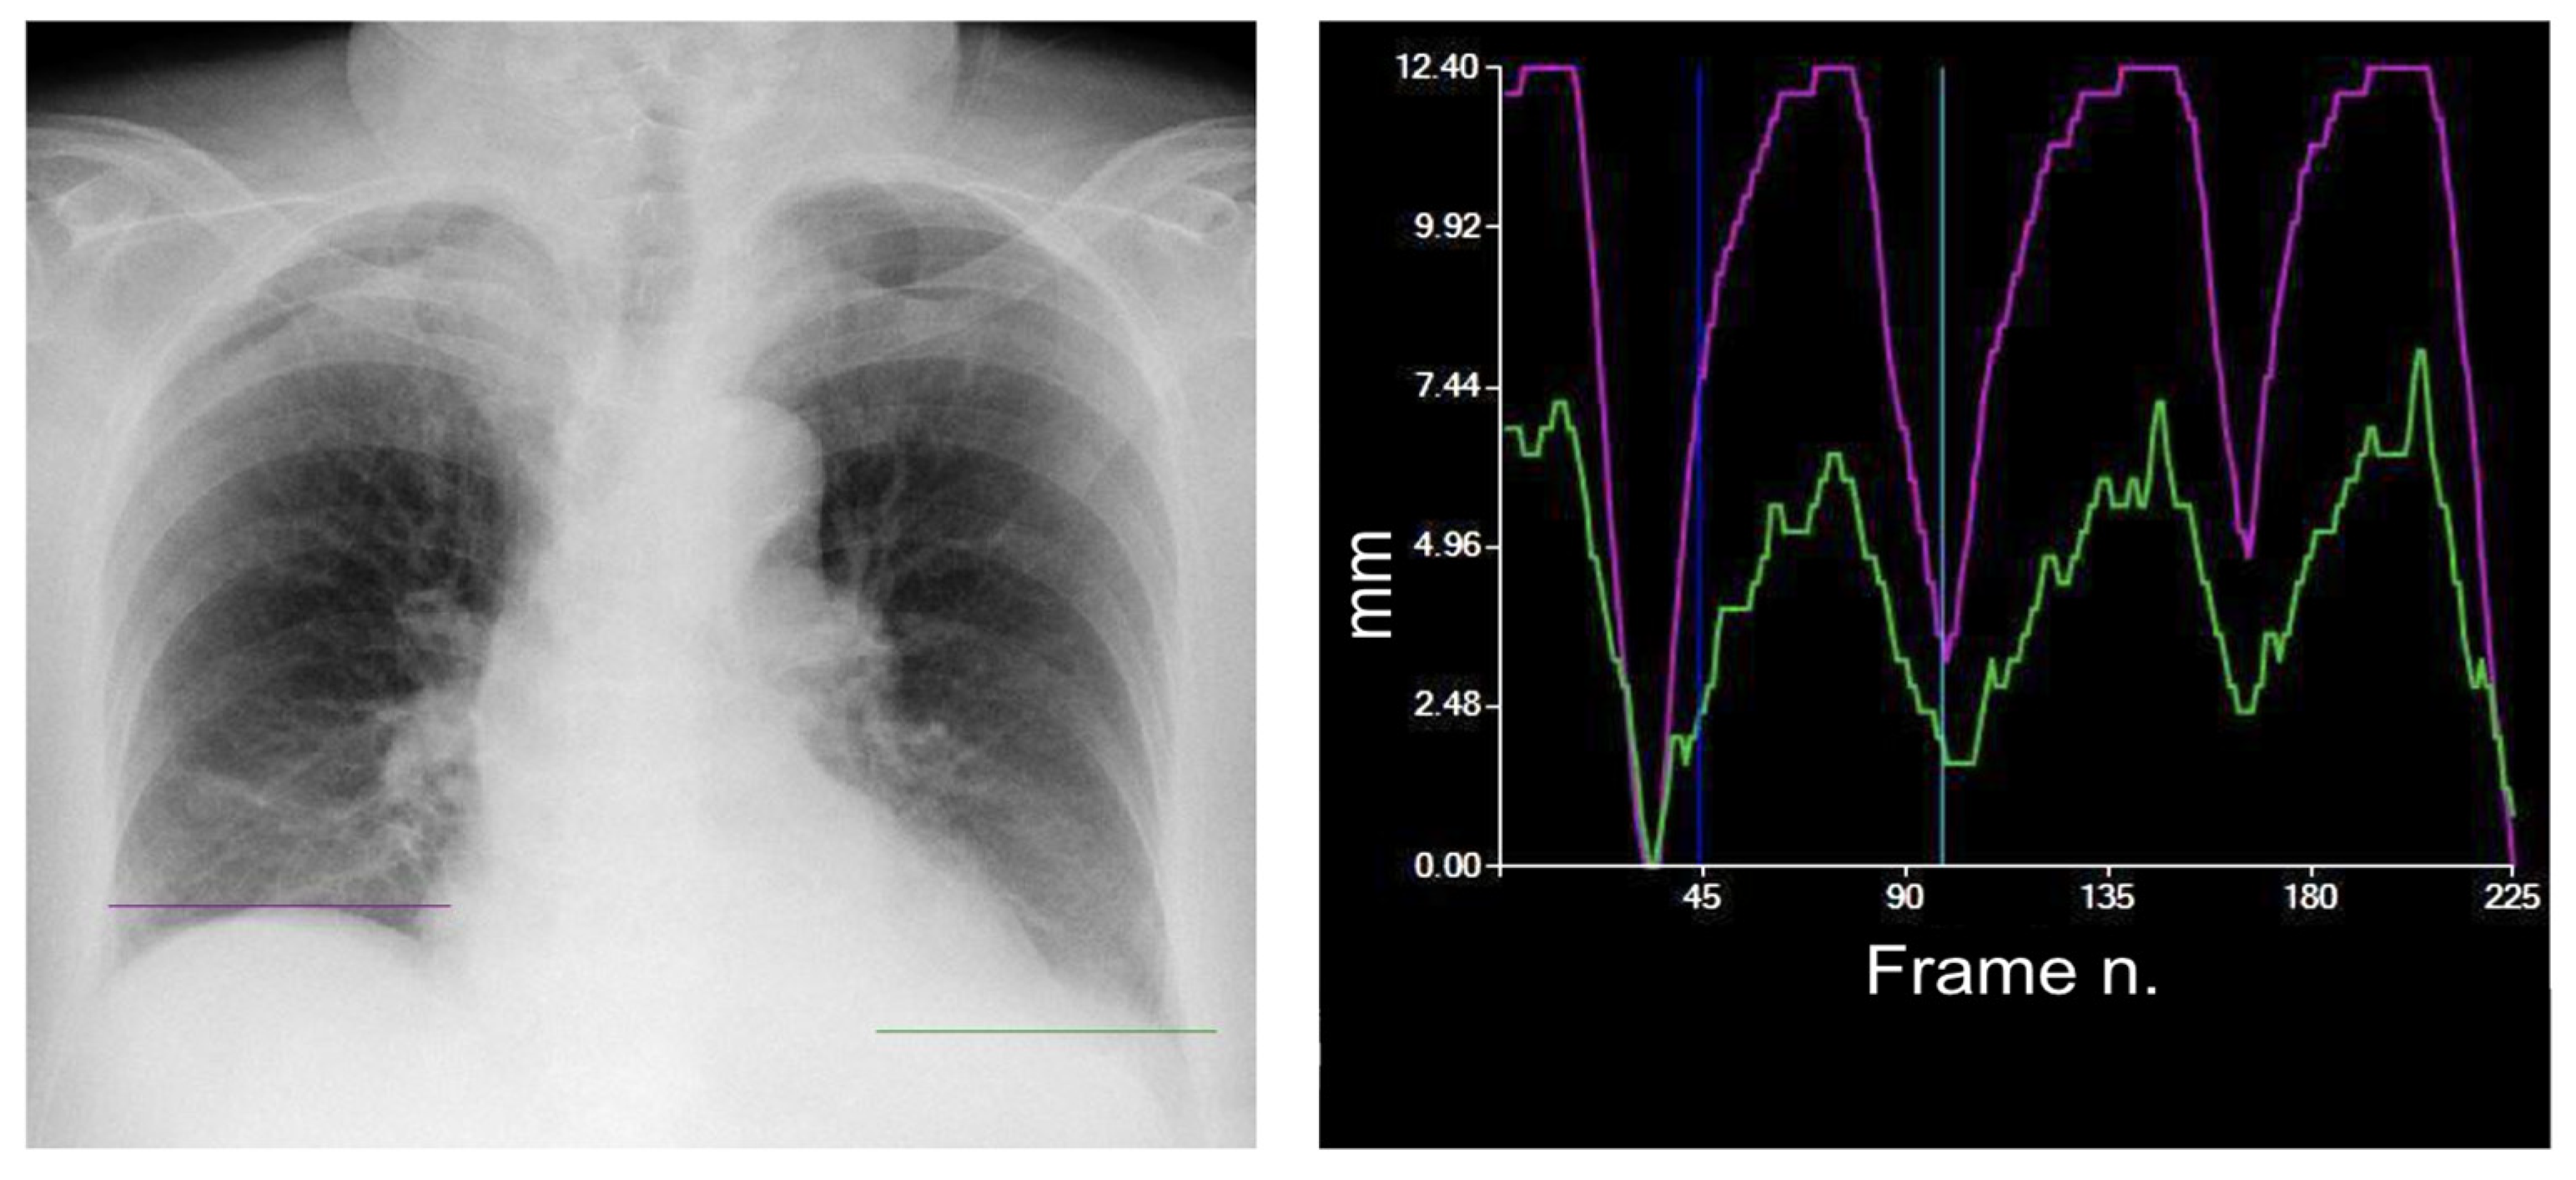

| DM-mode | Tracking diaphragm motion. Automatic calculation of the lung area and the relative changing rate (%). | Tracking of diaphragmatic domes represented in a motion–time graph. Area detection through an edge detection method in the post processing phase. | Diagnosis of diaphragm motion impairment and palsy. Automatic calculation of the respiratory rate. Analysis of lung dynamics in patients with restrictive/obstructive diseases. Follow-up of patients in pulmonary rehabilitation. |